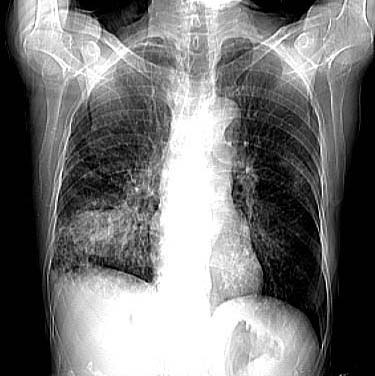

女:73岁;因一月前感冒后咳嗽,发烧,有大量脓痰,并且有恶臭味。

右肺下叶肺脓肿

补充_____伴双肺血行播散

谢谢辜兄为我们网站的兴旺所做出的杰出贡献!右下肺脓肿并双肺感染、右胸膜粘连。[emb21][emb20]

右下肺脓肿并双肺感染、右胸膜粘连。

右肺下叶示片状致密影密度不均,内见一空洞有宽液平,并可见壁结节周围示散在斑片模糊影,左下肺亦见一斑片模糊影,考虑 肺脓疡,肺癌不除外。

发烧,有大量脓痰,并且有恶臭味,空洞,大液平,比较典型的肺脓疡

该患者是我上个月作的,经正规抗炎治疗半月后平片显示吸收。{患者不愿ct复查}